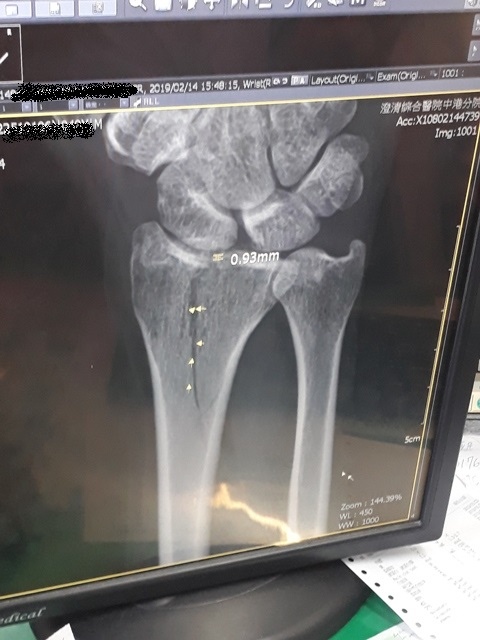

今日所拍的X光照↓

這三次回診的X光片,相較前兩次,今天已經癒合許多了↓

或許今天是228放假日,來醫院看病的人蠻多的,我們等了一段時間才被叫到。進到診間後,黃醫師調出X光資料,發現橈骨已癒合很多了,讓我感到很吃驚,兩個星期前還是很明顯的骨裂,現在已經看不太到了(小純說,一定是峰王膠原飲發揮了功效,這兩週內,膠原蛋白喝了八罐了)。黃醫師說,我的手腕護具可以拿掉了,我拿起護具後,黃醫師拉了我的手腕做一些轉動的動作,還是有些痛,黃醫師叫我要多做熱敷,手可以開始做復健了,也可以讓手開始做一些事情,但避免提重物,兩個星期後再回診看角度。